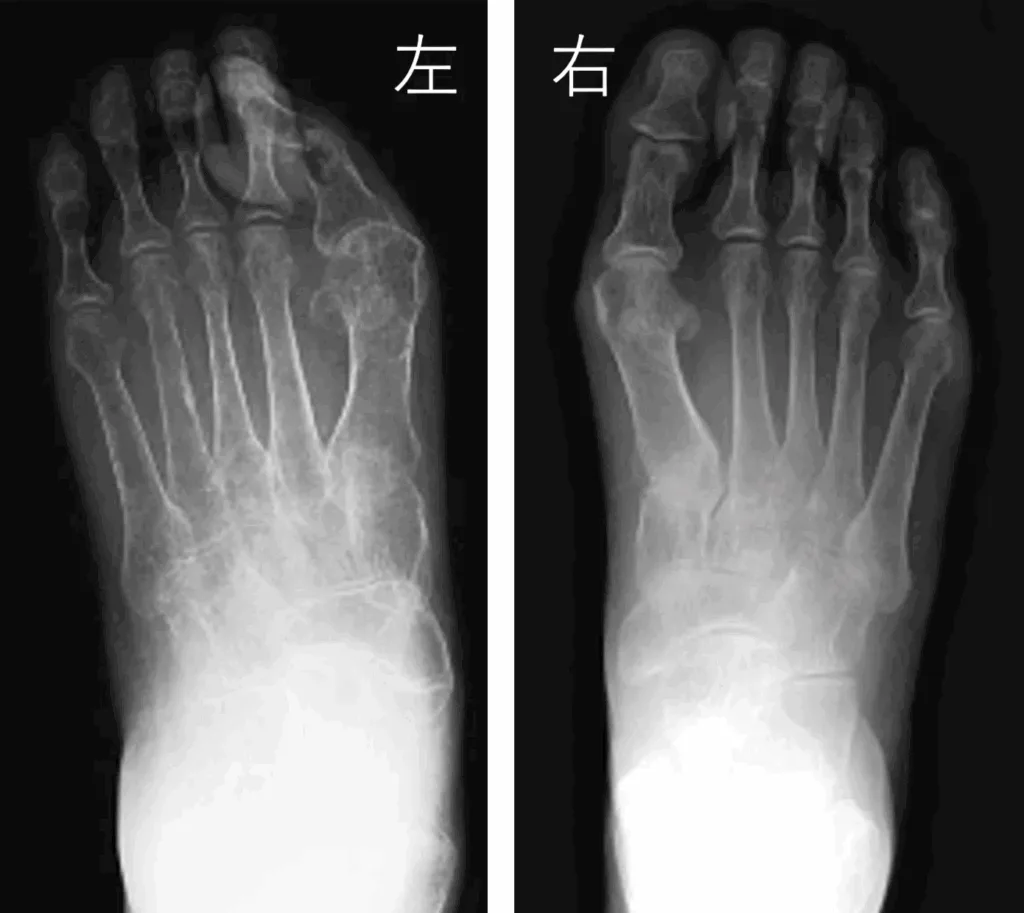

他覚的所見として、単純X線写真の骨萎縮所見や三相骨シンチグラフィーは有用であるとされています。そのほか、発汗量や定量的発汗軸索反射テストなどの血管運動障害所見や、2℃以上の皮膚温度変化も挙げられていますが統一されていません。

次の単純X線写真は、左が患側になります。右の正常な骨と比べて、左の骨が薄く見えると思います。このように骨が薄くなることを骨萎縮像(骨透亮像)といいます。